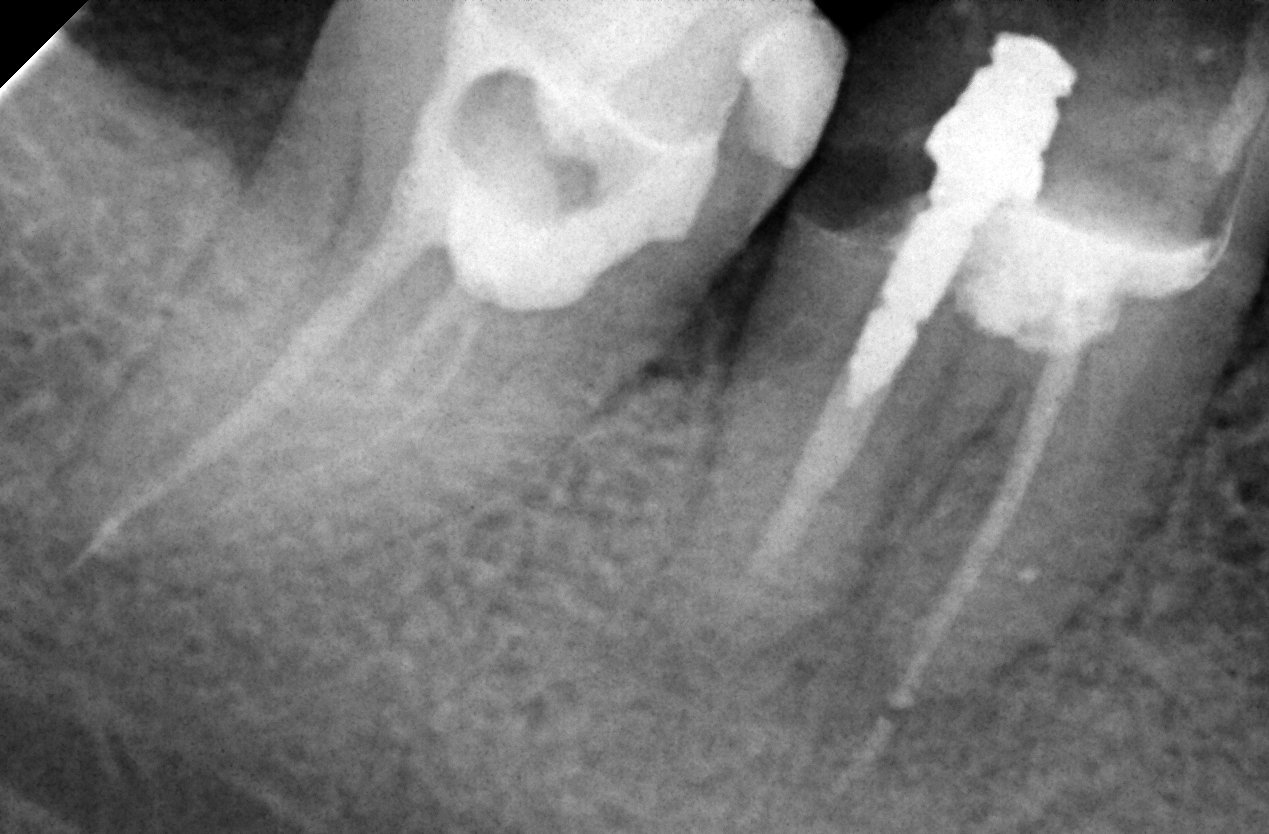

Здравейте. Към докторите във форума: в петък ми запълваха каналите на долен 8 зъб. При натиск обаче, има напрежение. Стоматоложката ми каза, че може да е поради препресване на зъбния канал. Моля за Вашето мнение, по начина на запълване на каналите на зъба: на снимката е този в ляво( без щифта)?